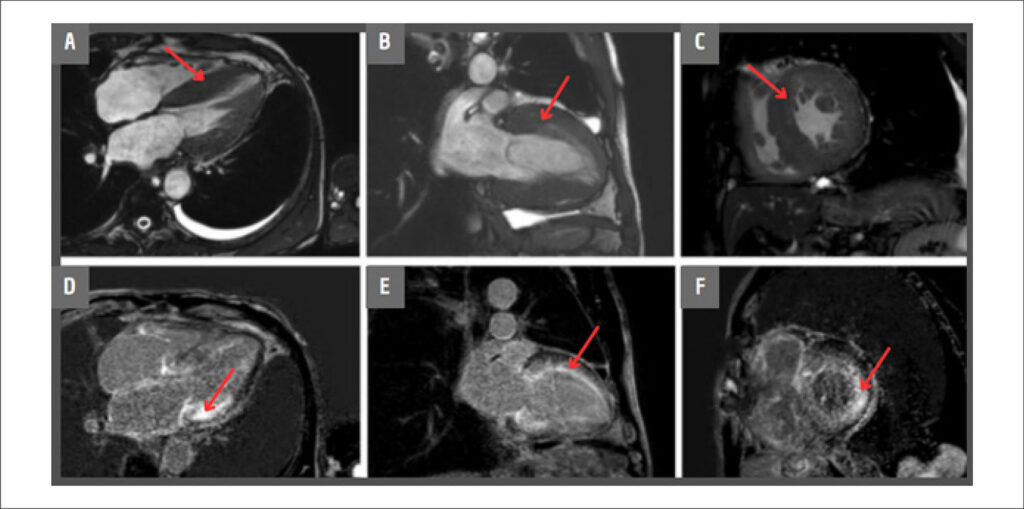

A Amiloidose cardíaca é uma cardiomiopatia restritiva causada pelo acúmulo de proteína amiloide no coração. Anteriormente considerada uma condição rara, avanços no diagnóstico não invasivo têm aumentado sua identificação entre pacientes com Insuficiência Cardíaca (IC). Atualmente, representa cerca de 13% dos casos de Insuficiência Cardíaca com Fração de Ejeção Preservada (ICFEP). Neste estudo, relatamos o caso de um paciente do sexo masculino, com 72 anos de idade, que compareceu à clínica relatando dispneia e fadiga em atividades de baixo esforço. Foram realizados exames laboratoriais que revelaram marcadores cardíacos aumentados, juntamente com evidência de hipertrofia ventricular na análise eletrocardiográfica. À imagem cardíaca, o ensaio de cadeias leves (AL) livres no soro e a biópsia endomiocárdica indicaram o diagnóstico de amiloidose por AL. Um modelo tridimensional foi construído com dados de ressonância magnética (RM). O modelo visa aumentar a conscientização sobre a amiloidose como possível diagnóstico diferencial de IC, além de promover a educação de pacientes e familiares, demonstrando as alterações estruturais típicas da doença.